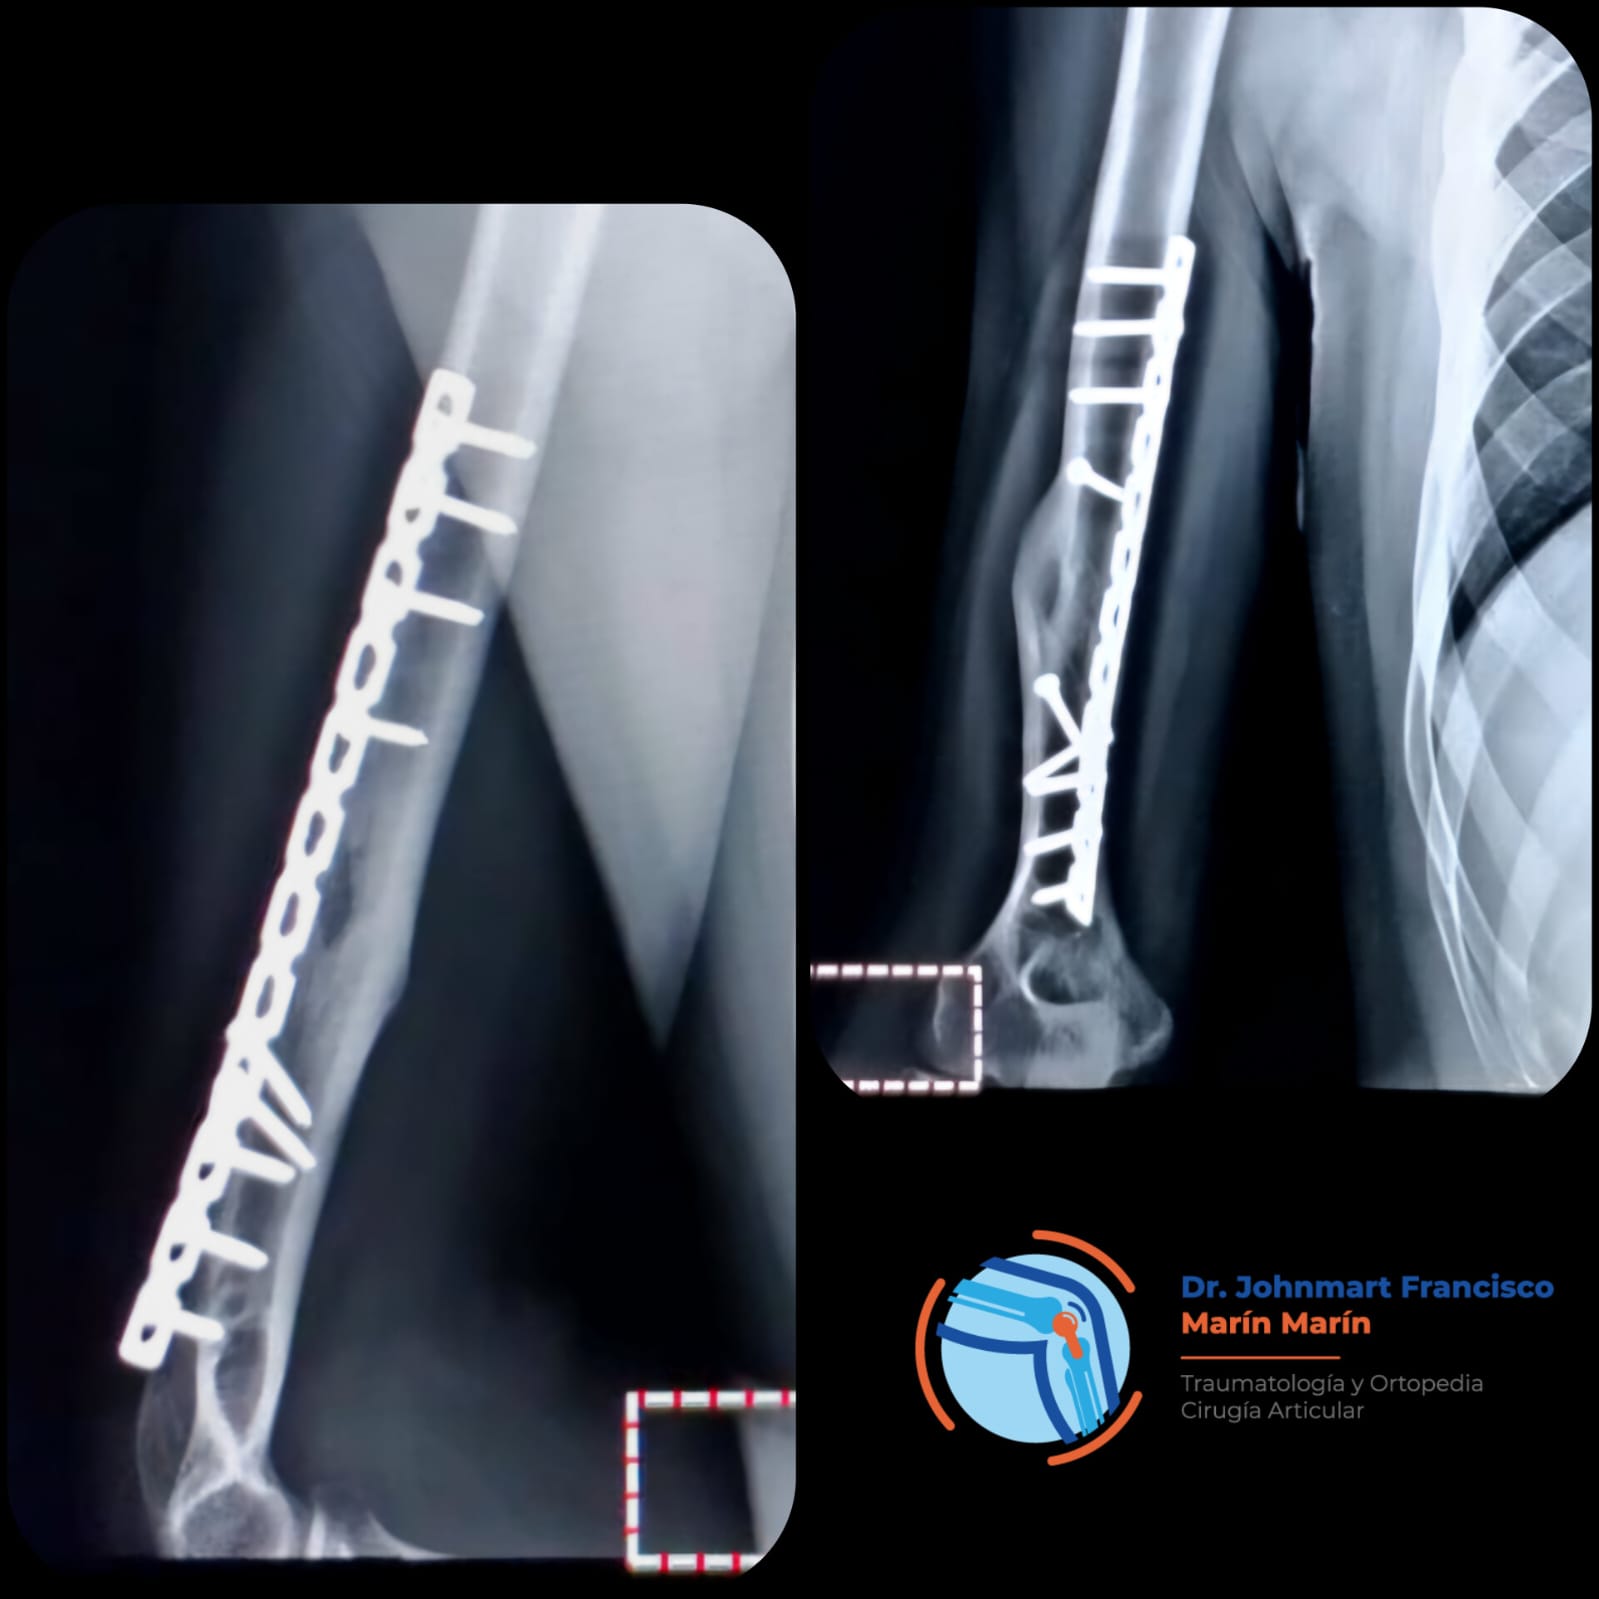

Atención a Lesiones

Lesiones Deportivas

Lesiones graves como fracturas, rupturas de ligamentos, esguinces o incluso luxaciones.